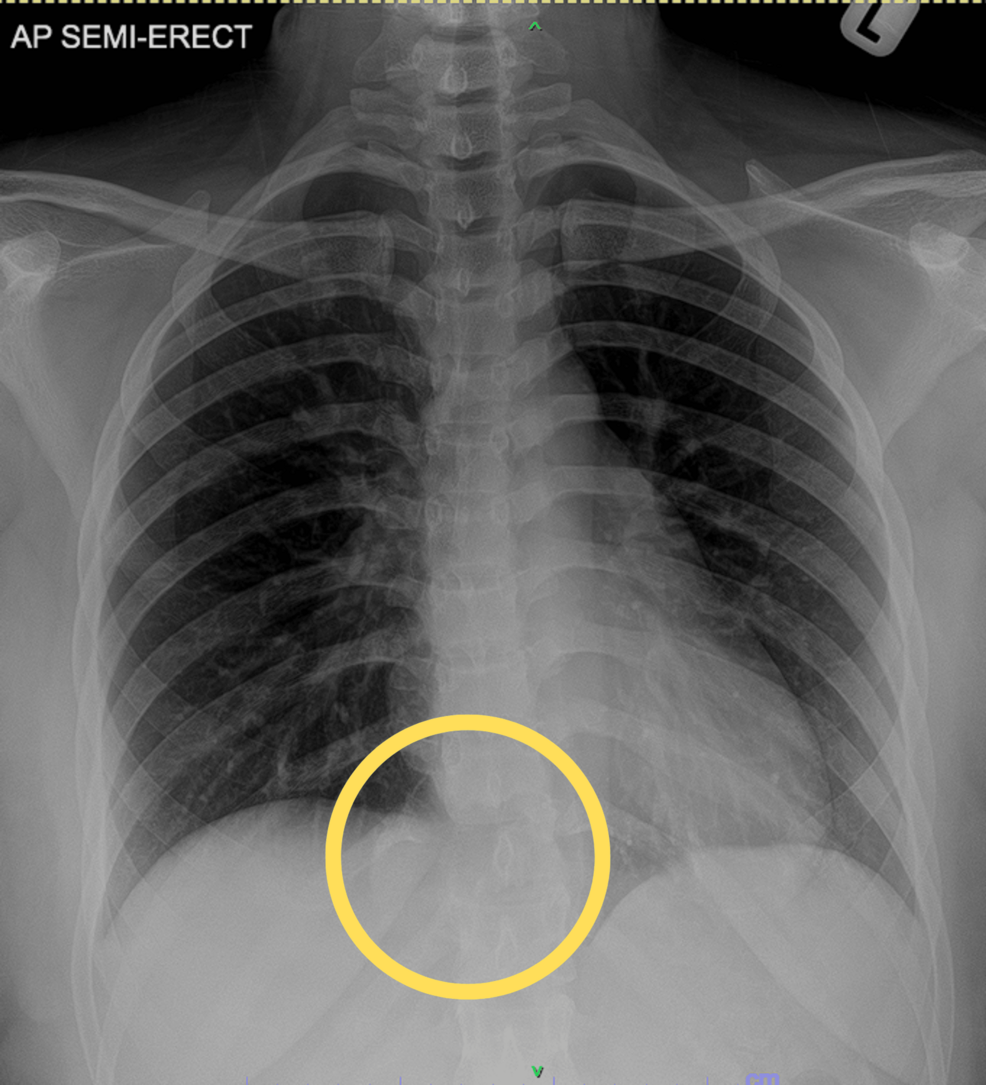

In Plain Sight: An Inconspicuous Case of a Giant Cell Tumor - The American Journal of Medicine